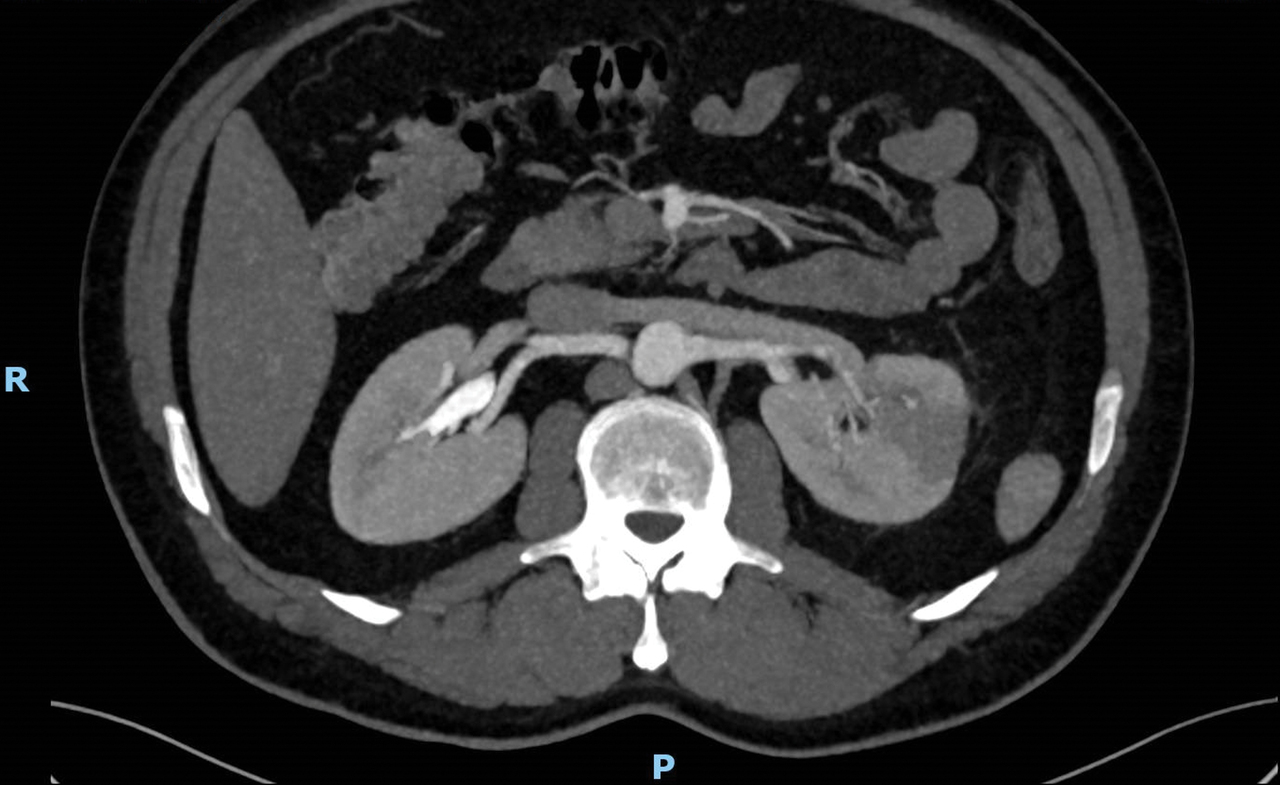

Homme 47 ans sans antécédents consultant pour une douleur lombaire gauche d’apparition brutale sans fièvre.

Quel est votre diagnostic ?